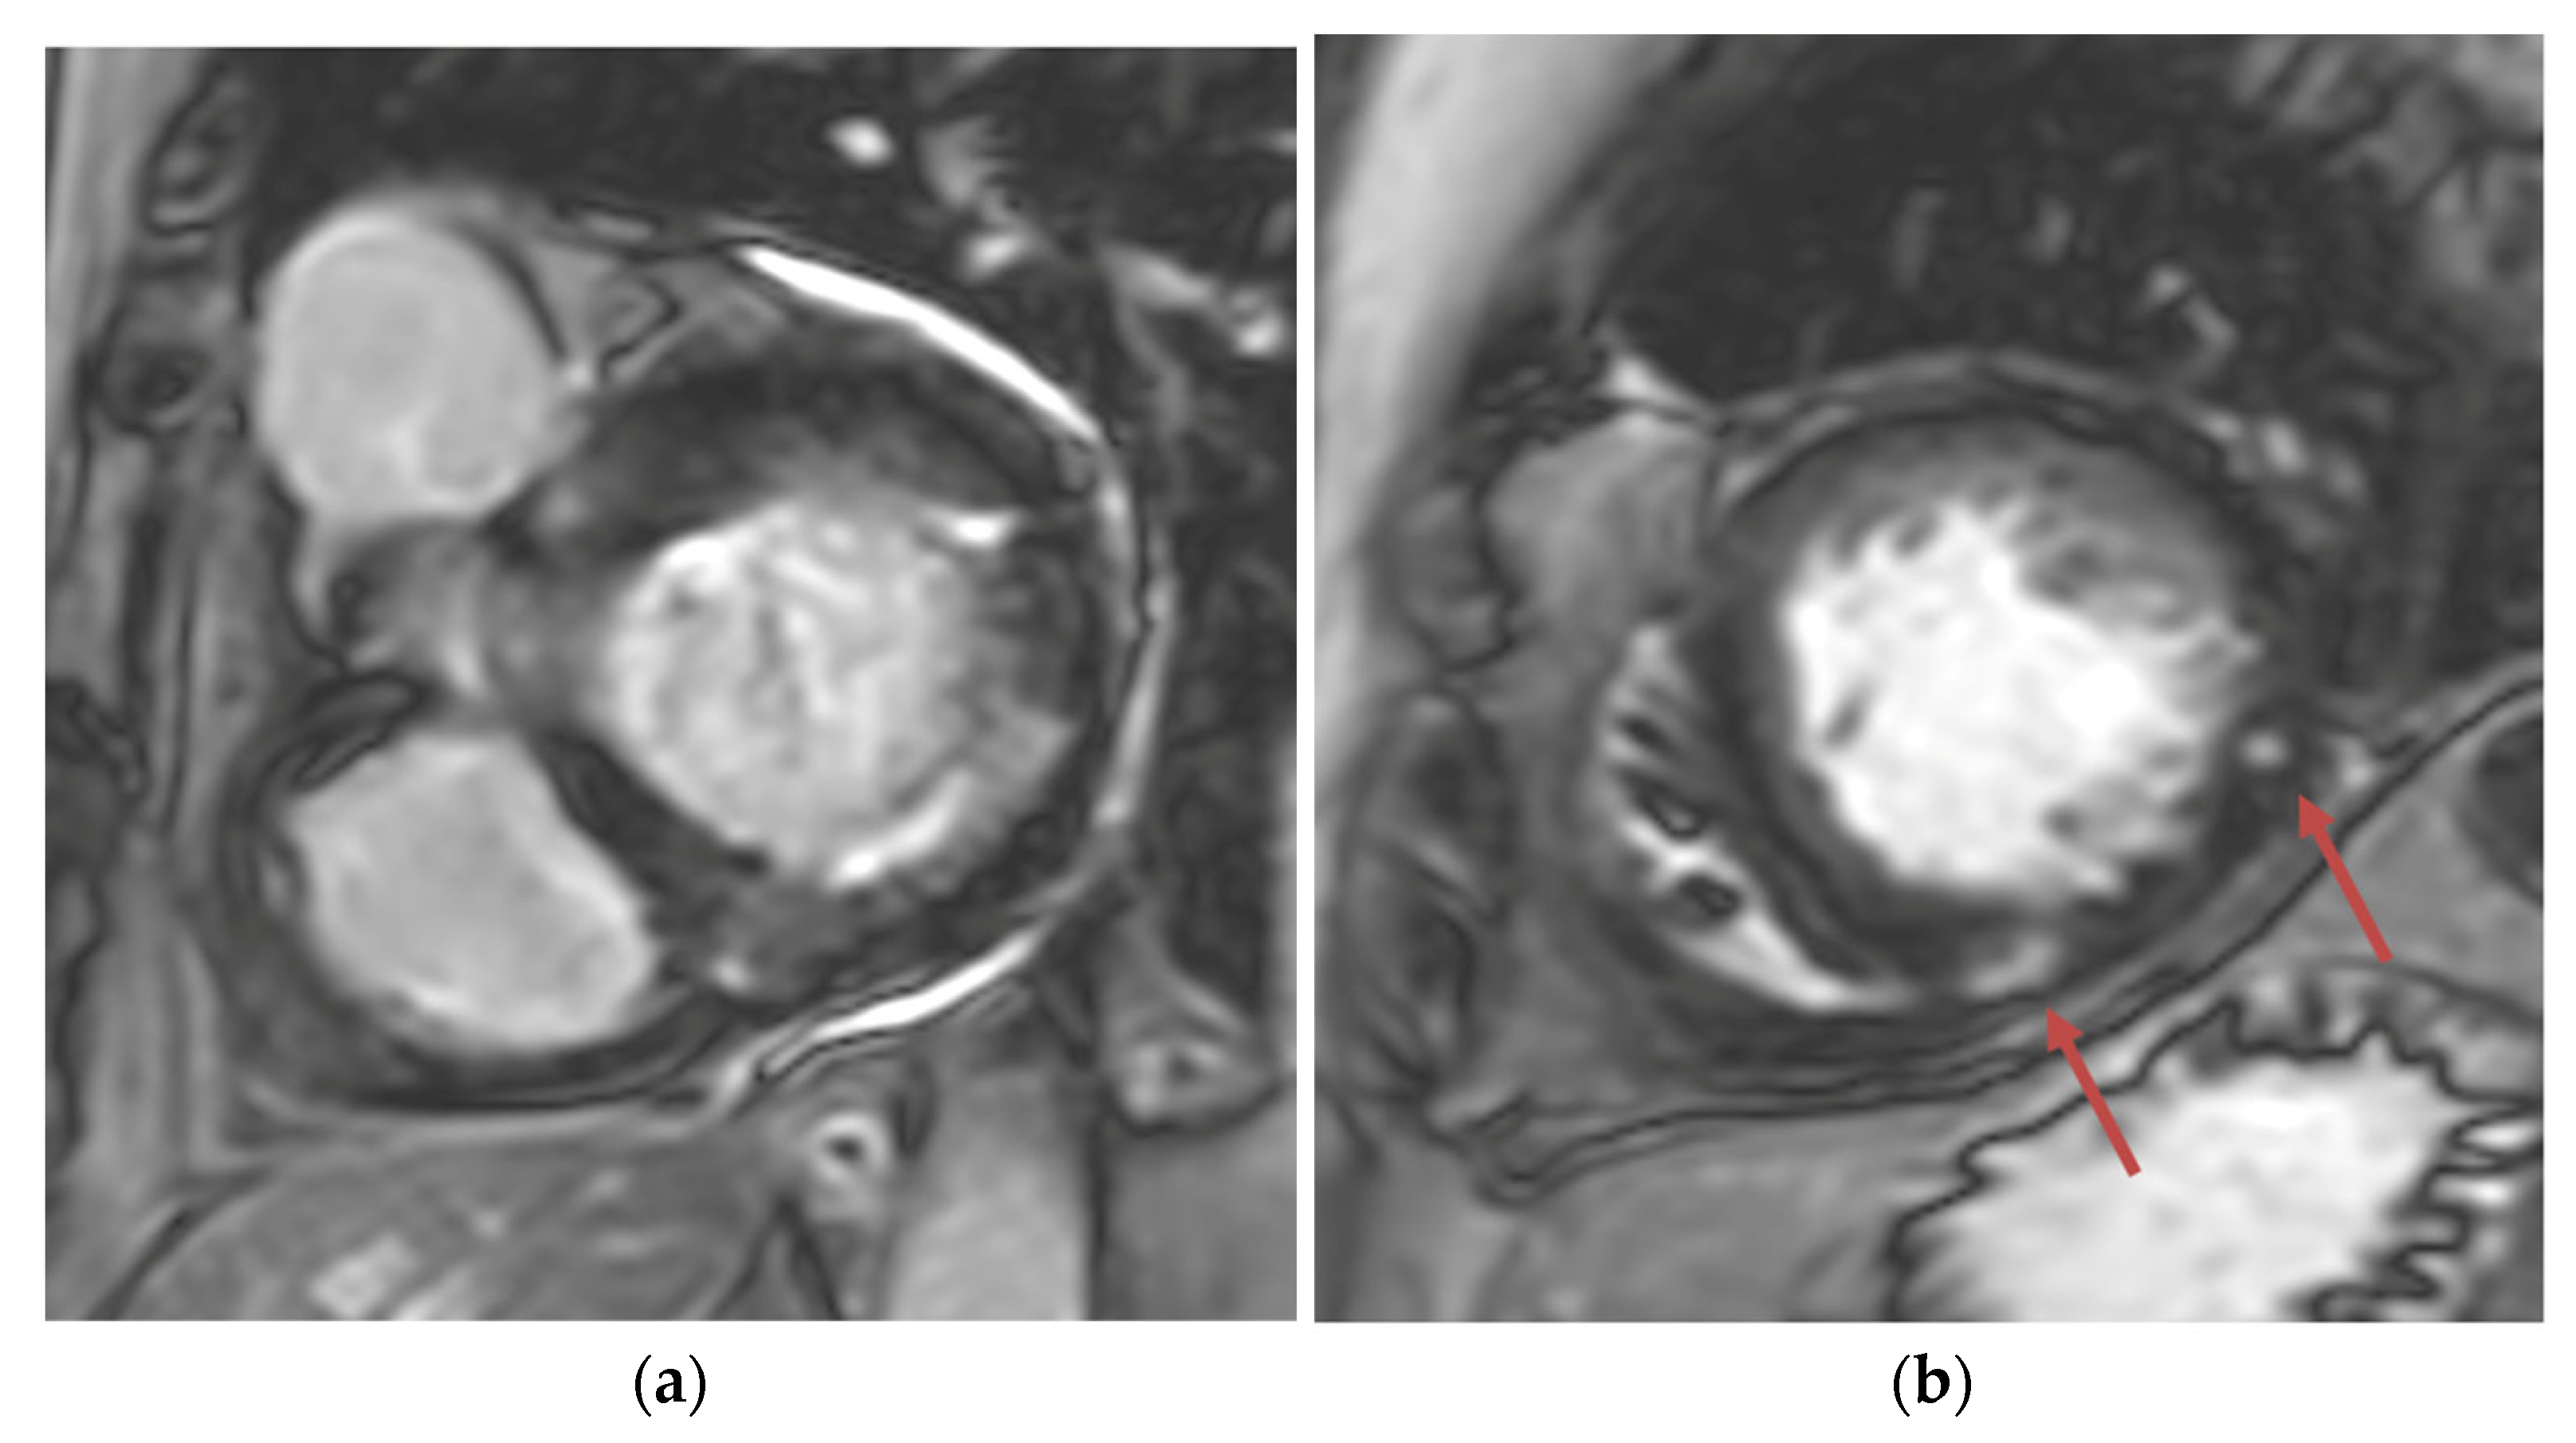

Transthoracic echocardiogram (TTE) showed severe asymmetric left ventricular hypertrophy, preserved left ventricular ejection fraction at 65–70%, systolic anterior motion (SAM) of the mitral valve (Figure 1 and Supplementary Video S1), left ventricular outflow tract (LVOT) obstruction with a peak velocity of 7.1 m/s at rest and an eccentric, posteriorly directed mitral regurgitant jet (Figure 2). Pharmacological myocardial perfusion SPECT with gated imaging was obtained one year prior to presentation and showed normal myocardial perfusion, left ventricular volume and systolic function. Cardiac magnetic resonance imaging showed left ventricular hypertrophy with a maximal thickness of 1.7 cm at the mid-ventricular septum and late gadolinium enhancement in the lateral and inferior half of the left ventricle, the basal inferolateral wall, the apical lateral walls and the apical anterior wall (Figure 3a,b). These findings were consistent with a diagnosis of HCM with outflow tract obstruction; thus, the patient was started on beta blockers.

Figure 3. (a) Short-axis phase-sensitive inversion recovery showing patchy subendocardial late gadolinium enhancement in basal inferolateral wall; (b) Short-axis phase-sensitive inversion recovery showing patchy intramyocardial late gadolinium enhancement (red arrows).